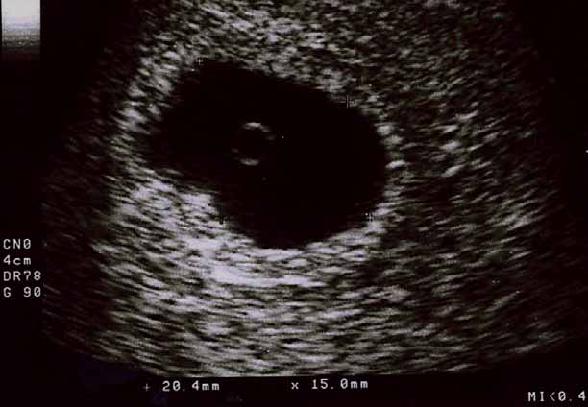

GS (gebelik Kesesi, Gestasyonel Sac): En erken olarak transvajinal ultrasonda gebelik 4 bucuk -5 haftalık olduğunda görülebilir. Karından yapılan ultrasonda gebelik 6 haftalık olduğunda görülebilir. GS'ye göre gebeliğin kaç haftalık olduğunun belirlenmesi tavsiye edilmez bunun yerine CRL ölçümü daha kullanışlıdır. GC yani gebelik kesesi düzensizse yani yuvarlak izlenmiyorsa gebeliğin düşükle sonuçlanma riski artmıştır. gebelik kesesi çok küçük ise içerisinde ebmriyo görülmez sadece kese şeklinde izlenir. gebelik kesesi 1 cm boyuta ulaştığında içerisinde yolk kesesi izlenir, 1.5 cm boyuta ulaştığında içerisinde embriyo da izlenebilir.

YS (Yolk kesesi, Yolk sac): Plasenta gelişmeden önce anne ve bebek arasındaki madde değişimini sağlayan yolk kesesidir. gebelik kesesi 1 cm boyuta ulaştığında içerisinde yolk kesesi görünür hale gelir. gebelik kesesinin kenarında ufak bir kese şeklinde izlenir. gebelik kesesi 1 cm'den fazla büyüklüğe varmasına rağmen yolk sak görünmüyorsa bu gebeliğin düşükle sonuçlanma riski artmıştır. Aynı şekilde yolk sac 6 mm'den fazla büyümüşse bu da yine gebeliğin düşükle sonlanacağını gösterir.